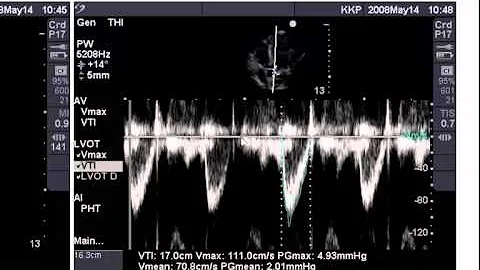

Estimating Ejection Fraction With Point Of Care Echo

A video tutorial aimed towards Emergency Medicine Resident Physicians which demonstrates three methods for estimating LV EF ...